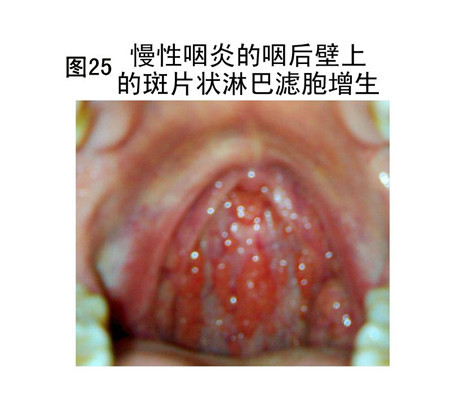

慢性咽喉炎圖片

慢性咽喉炎相關文章